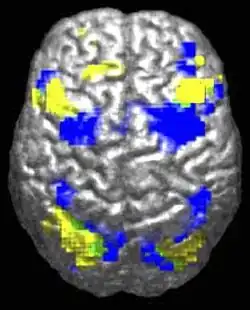

Des différences au niveau du cerveau ont été observées chez les personnes autistes, apportant une signature anatomique à la définition antérieure par des critères cliniques. Les études en neurosciences ont montré des différences dans l’organisation du cortex[38],[39], au niveau des dendrites (arborescences des neurones) et des synapses (connexion entre neurones), voire des modifications plus larges de structures cérébrales. Il est possible que les différences corticales apparaissent au cours d'un stade de développement anténatal[38].

En corrélation avec les différences fonctionnelles observées au niveau comportemental, les études d'Eric Courchesne et de son équipe relèvent que les enfants autistes ont un nombre de neurones plus élevé de 67 % en moyenne dans le cortex préfrontal[40], et une croissance cérébrale plus importante que la moyenne au niveau des lobes frontaux, ce qui s'est traduit dans la littérature scientifique antérieure par des observations de périmètre crânien plus élevé[41].

Cependant, le , dans une étude basée sur des données par imagerie par résonance magnétique (IRM), des chercheurs de l'Université Ben-Gourion du Néguev et de l'Université Carnegie-Mellon (États-Unis) ont estimé que les différences anatomiques entre le cerveau de personnes autistes de plus de 6 ans et celui de personnes du même âge non autistes sont indiscernables[42],[43]. Pour arriver à ce résultat, ces chercheurs ont utilisé la base de données Autism Brain Imaging Data Exchange (ABIDE), qui a permis pour la première fois de procéder à des comparaisons de grande échelle de scanners IRM entre des groupes de personnes autistes et des groupes contrôle[44]. Cette base de données est une collection mondiale de scanners IRM de plus de 1 000 personnes, pour la moitié autistes, âgés de 6 à 35 ans[45].